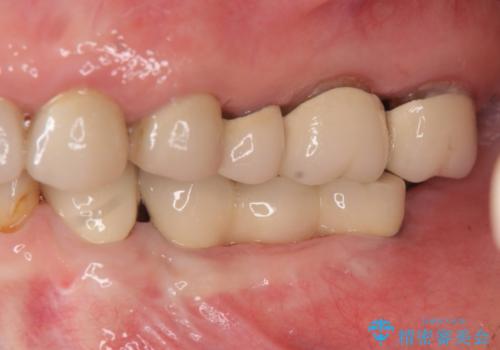

歯を失い噛めない、インプラントによる咬合機能回復

- 歯を失い噛むことができないことを悲観され来院されました。

他院で作製した入れ歯も嘔吐反射により気持ち悪くてはめていることができず、残存した右側の歯の負担は甚大です。

咬合機能を回復し、満足して食事を行えるようインプラント治療を計画します。